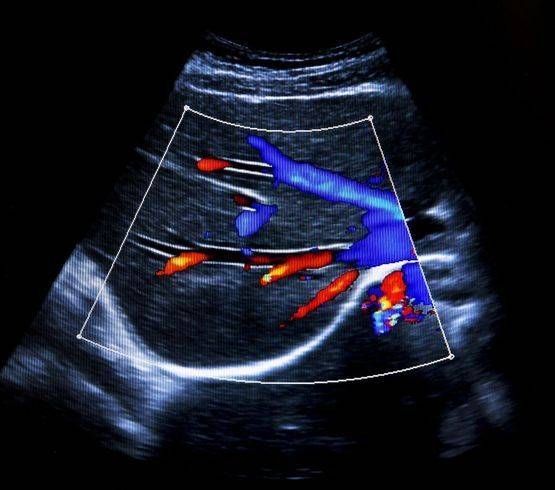

Doppler artériel et veineux

Nous intervenons pour les recherches de thromboses veineuses et artérielles, de dilatation des voies urinaires et biliaires, de masses abdominales, mammaires et des parties molles, d'épanchement, le bilan de douleurs abdominales et articulaires et de pathologie ganglionnaire.